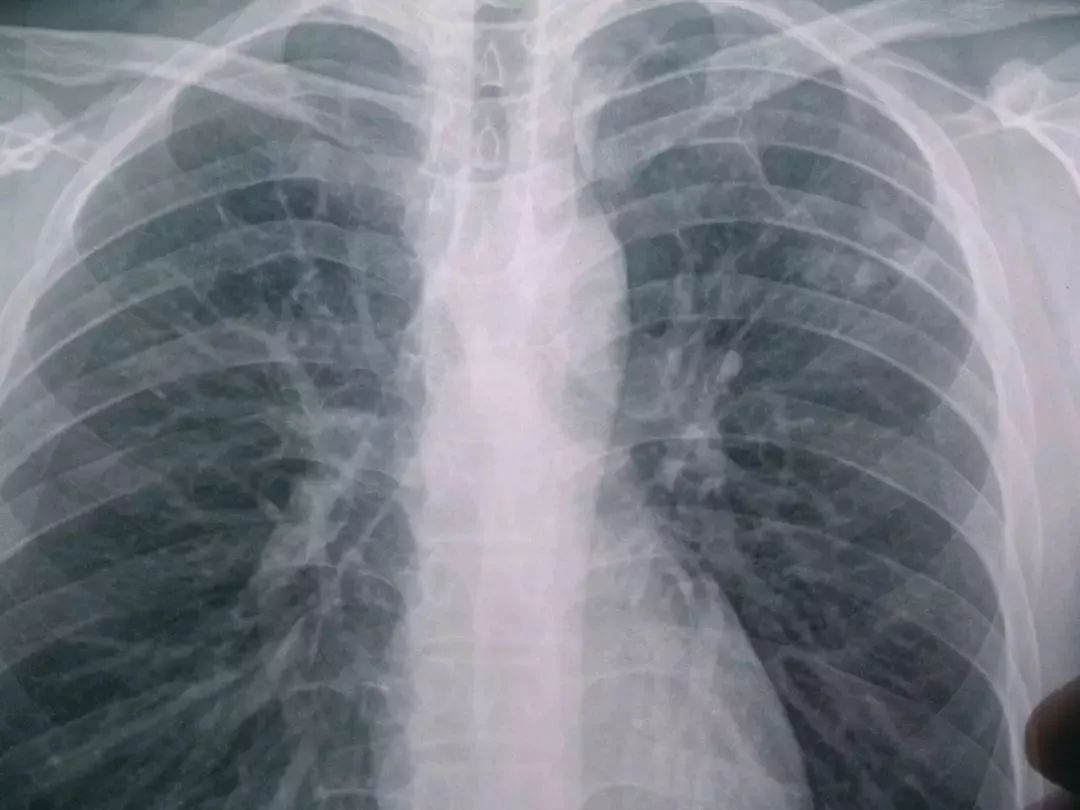

肺结核最严重的图片

肺结核最严重的图片,正常肺与肺结核图片

肺结核x光片

肺结核图片